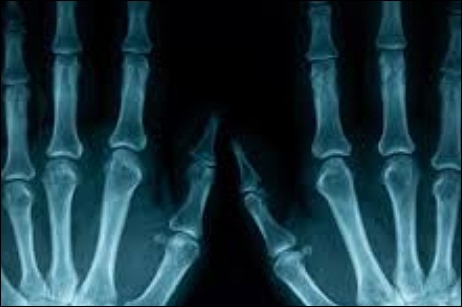

손가락 마디 통증 2 : 관절염

두번째 손가락 통증의 원인은 관절염입니다. 손가락도 다른 관절과 마찬가지로 관절염이 쉽게 걸릴 수 있는 부위입니다. 그 이유는 손가락에 있는 관절은 자주 쓰기도 하고 요즘은 스마트폰으로 인해 손가락 관절에 힘이 많이가 무리가 되기 때문입니다. 예전에는 나이 드신 어르신분들이 많이 걸리셨는데 요즘은 젊은 세대들도 조심하셔야 된다고 합니다.

손가락 마디 통증 3 : 류마티스 관절염

세 번째 원인은 류마티스 관절염입니다. 류마티스류머티즘 관절염이란, 정확한 원인이 아직까지 밝혀지지 않은 관절염인데, 유전적인 원인, 스트레스, 면역성 약화로 인해 생길 수 있는 질병 중 하나라고 합니다. 류마티스 관절염이 생기게 되면 손가락 관절에 심각한 손상을 입을 수 있으며, 손가락이 휠수도 있고 모양이 변형되는 특징도 가지고 있다 합니다.